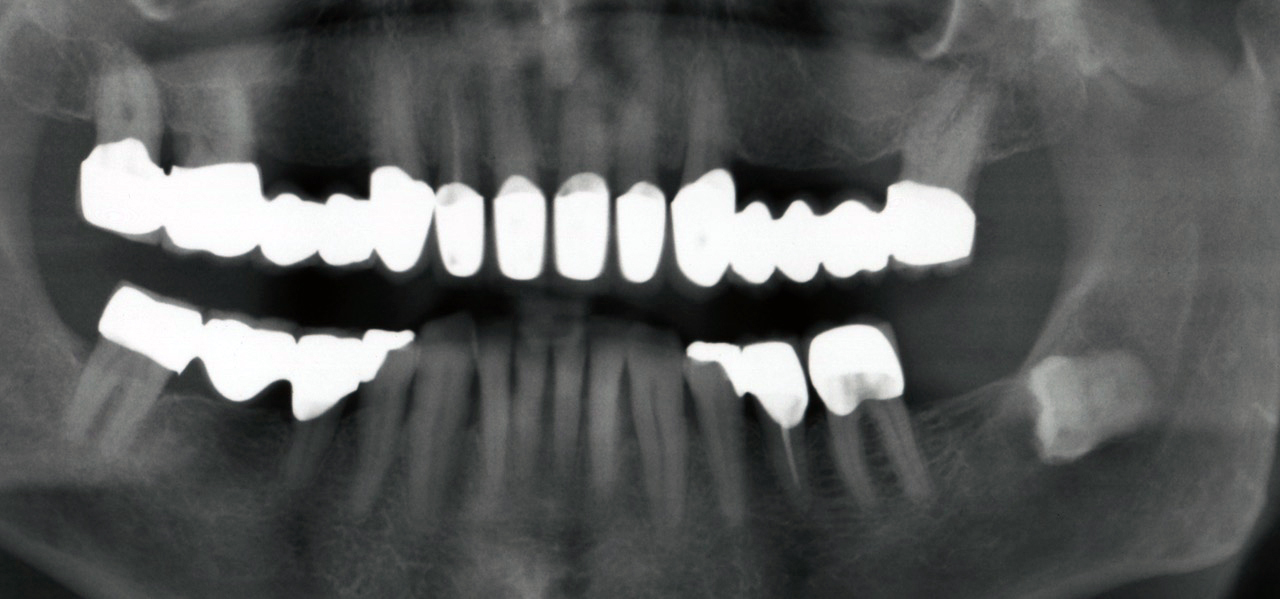

Unsere Zähne sind einzigartige Festkörper, die diese Körperhülle durchstoßen – das existiert im menschlichen Organismus nur an dieser Stelle. Zähne wurzeln im Knochen und ragen in den von Bakterien besiedelten Mundraum (s. Abb. 1).

Eine professionelle Zahnreinigung (PZR) ist hilfreich, weil sich auf gereinigten Zähnen Plaque (Zahnbelag) leichter im Zaum halten lässt; Plaquefreiheit von eigener Hand herzustellen, ist mühsamer. Stellt der Zahnarzt einen Code 3 (Zahnfleischtaschen von 3,5 bis 5,5 mm) oder sogar Code 4 (Zahnfleischtaschen tiefer als 5,5 mm) fest, muss allerdings eine gründliche Untersuchung durchgeführt werden, um das Ausmaß der Erkrankung und den Behandlungsumfang feststellen zu können. Dafür werden die Zahnfleischtaschen und der Gewebeverlust an allen Zähnen gemessen und Röntgenbilder angefertigt.

Eine erfolgreiche Behandlung der parodontalen Entzündung kann nicht nur die lokalen Symptome der Erkrankung des Zahnhalteapparats und damit Zahnverlust vermindern (s. Abb. 3 u. 4), sondern auch die Stoffwechseleinstellung verbessern. Die Reduktion des HbA1c-Werts lag bei Typ-2-Diabetikern drei Monate nach einer nichtchirurgischen Parodontitisbehandlung zwischen 0,4 und 0,5 Prozent, was durchaus nennenswert ist.